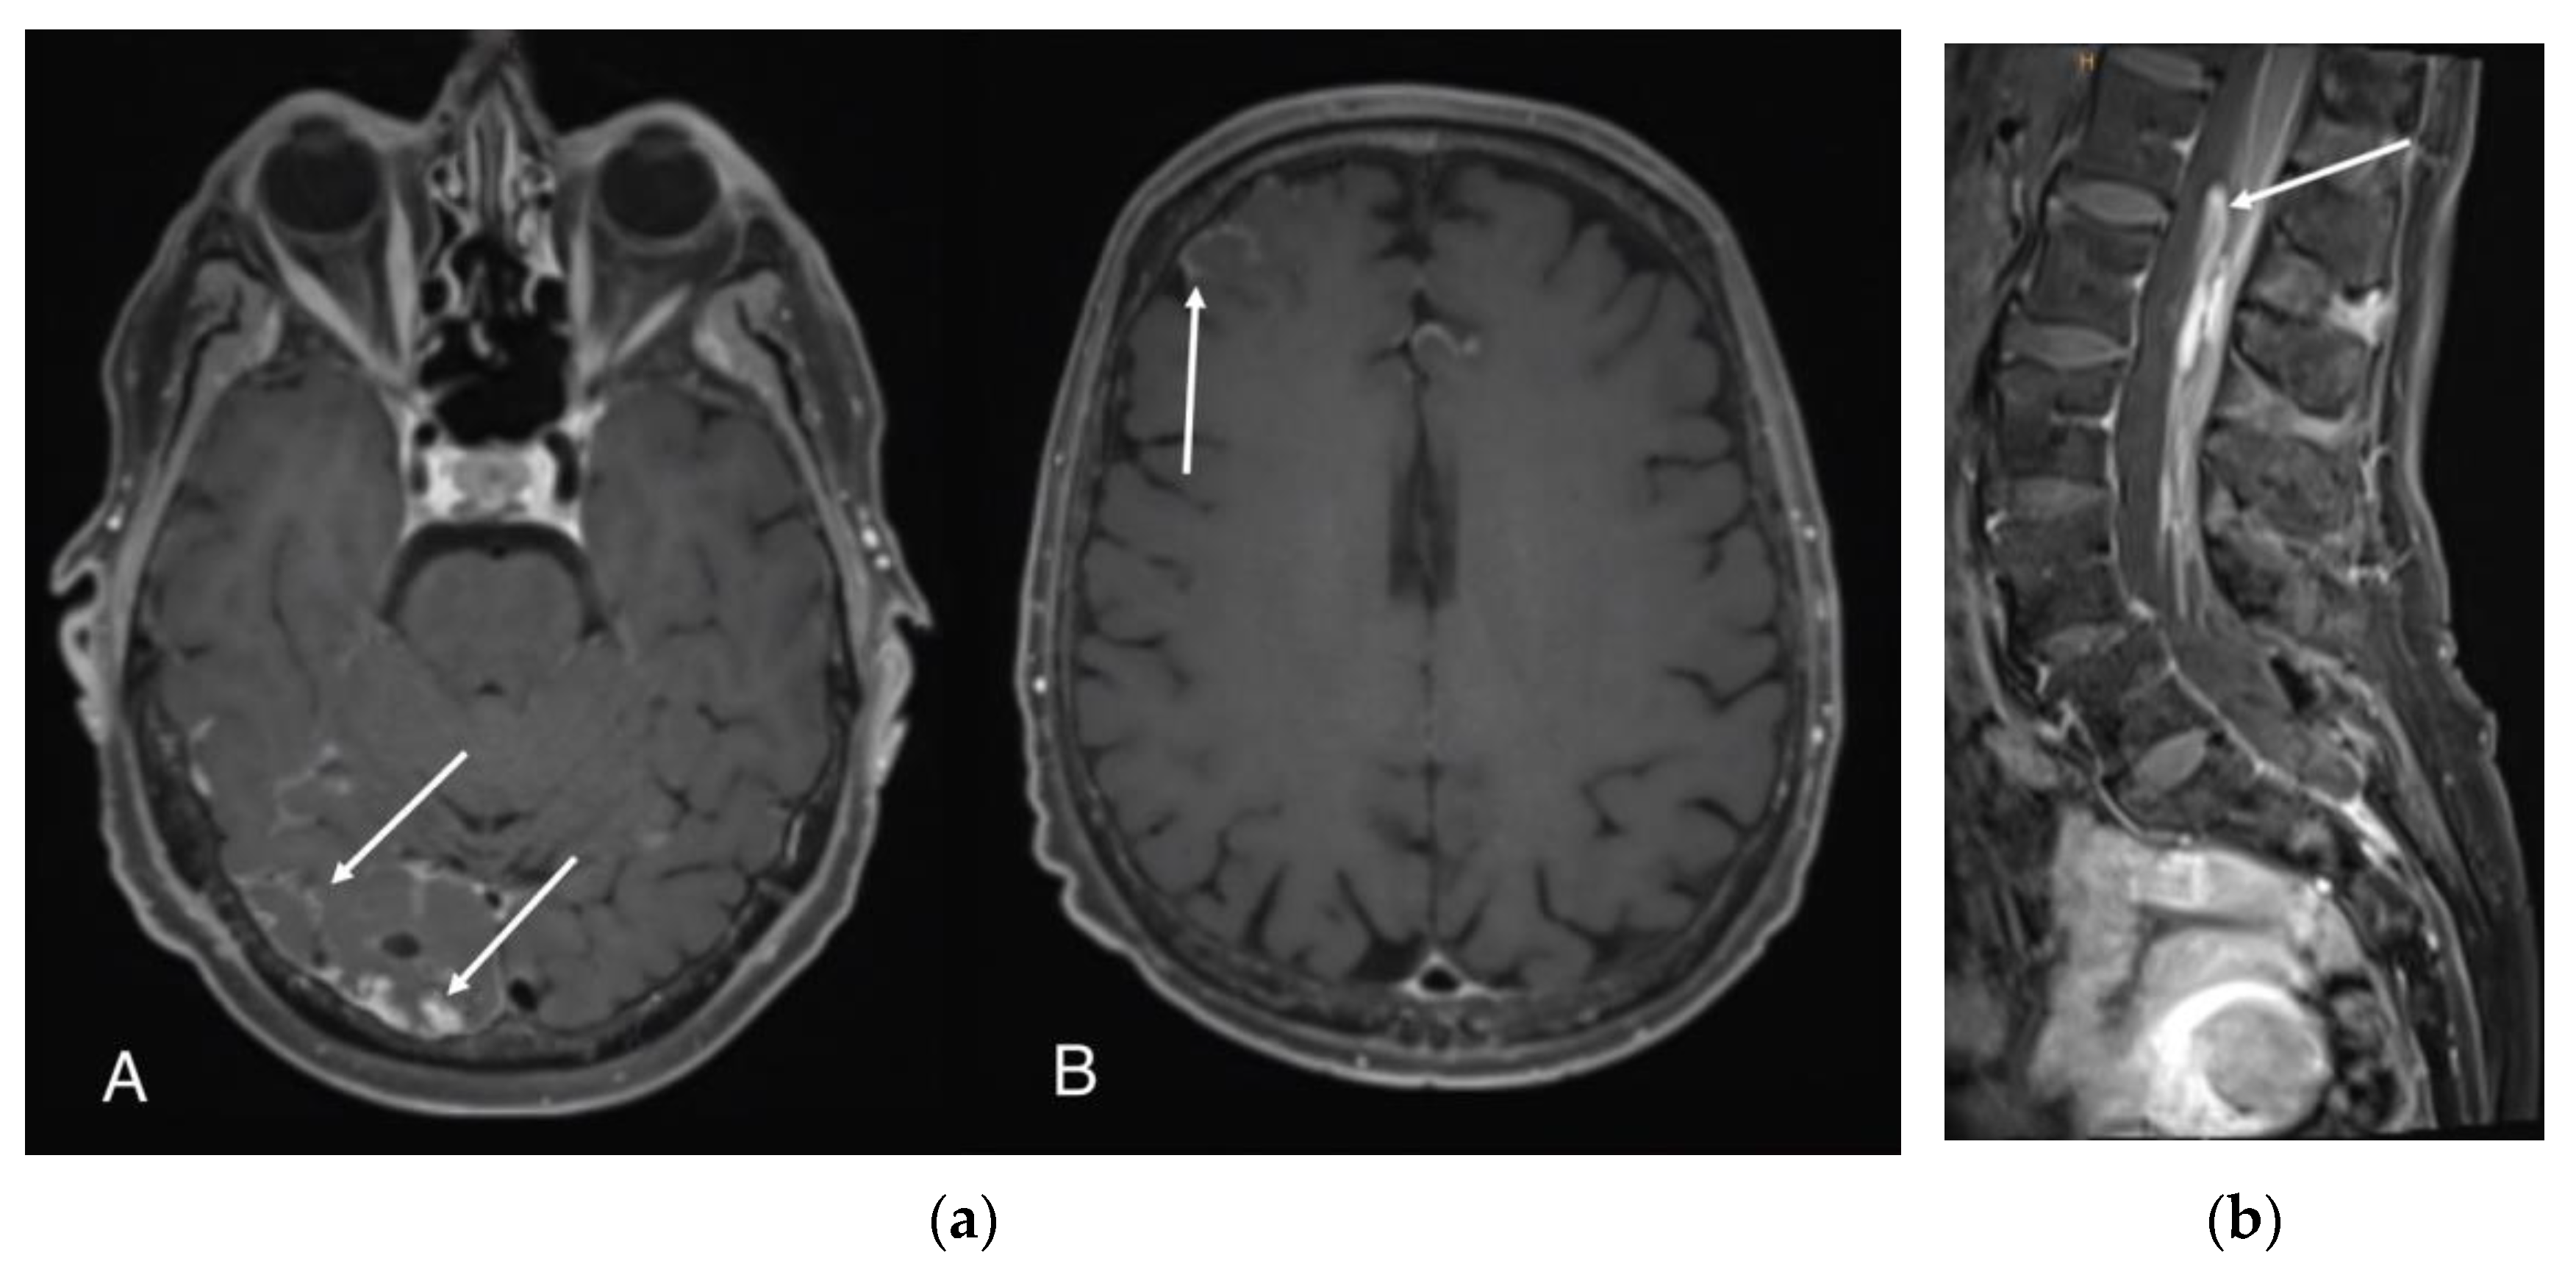

5.1.3. MRI